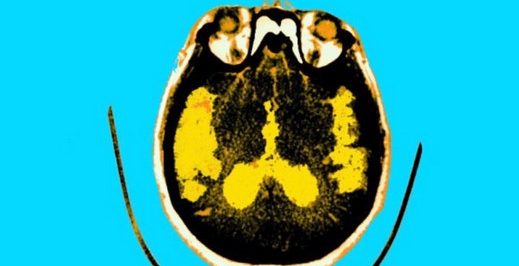

Alzheimer’ın diyabetik bir hastalık olduğu görüşü, on yıla yakındır tıp çevrelerinde giderek daha fazla ağırlık kazanıyordu. Biriken kanıtlar o kadar güçlü ki birçok uzman artık Alzheimer’ı tip 3 diyabet olarak adlandırmakta sakınca görmüyor. Bu şaşırtıcı gelmemeli. İnsülin sadece vücudun somatik hücrelerine glikoz alımı sinyali vermiyor; aynı zamanda beynin glikoz alımını da yönetiyor. Ve beyne enerji veren şey glikoz. Beynin birincil enerji molekülü. Bir süredir beynin kendisinin belirli miktarda insülin ürettiğini ve beynin çeşitli kısımlarının insülin reseptörleri açısından zengin olduğunu biliyordu.Bilişsel gerilemenin hem obezite hem de insülinle ilgili metabolik anomalilerle ilişkili olduğu da belirlenmişti. (Örneğin bkz. Whitehall II kohort çalışması.) Mental gerileme ile diyabet arasındaki ilişki aslında yüzlerce yıl önce hekim Thomas Willis tarafından gözlenmişti. (Öte yandan 1935’te Amerikalı psikiyatr William Claire Menninger, “psikojen diyabet” olduğunu varsaymış ve bir “diyabet kişiliği” tarif etmişti.)

Beyin insülinindeki anomalilerin Alzheimer hastalığını tetiklediğini gösteren kanıtlar 2011’de yayınlanan Hisayama Çalışmasına ait. Bu çalışma başlangıçta hastalığa sahip olmayan 1017 hastanın 15 yıl boyunca takibi üzerinden gerçekleştirildi ve bulgular şu şekildeydi: Tüm nedenlere bağlı demans, Alzheimer hastalığı (AD) ve vasküler demans (VaD) için yaş ve cinsiyet açısından düzeltilmiş görülme sıklığı, diyabetli deneklerde normal glikoz toleransına sahip olanlardan belirgin derecede yüksekti.